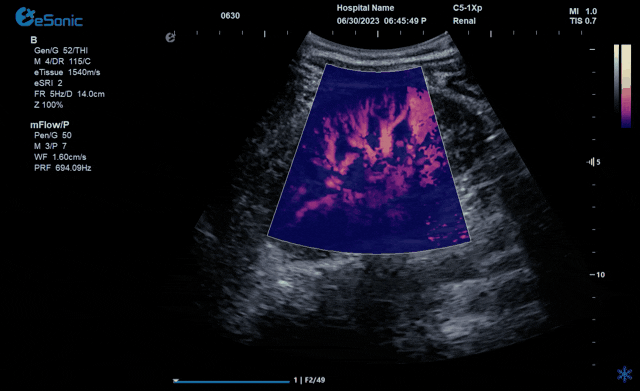

百乐博平台医疗的eHertz系列彩色多谱超声诊断系统凭借强大的RawVision?原数精准平台和SDBeam?软波声束合成技术推出专属的mFlow ?超微血流显像技术,该项技术可专用于极低速血流成像。

彩色多普勒血流(CDFI)检查时,通常会将滤波器的频率设置为大约50hz,并随时调整标尺和增益,以便在背景噪声发生前显示小血管,mFlow? 具有更丰富的血流信号,使观察者能够检测到一些CDFI无法观察到的血流信号。

从影像学原理来看,低速血流检测的主要困难在于受血管周围的运动的影响。为了消除组织运动中的伪影,彩色多普勒血流显像采用壁滤波器。然而,此时微血管和低速血流与病变的临床信息也会被过滤。因此,CDFI只能显示直径最低大约0.2mm的血管和相对高速的血流。为突破这一困境,mFlow? 超微血流显像技术采用了一种更智能和独特先进的算法,能够有效地区分组织运动和血流运动产生的多普勒信号。mFlow? 应用更高的信噪比显示极低速血管和血流,由此可以检测到直径大约0.1mm左右的血管和速度低于1cm/s的血流。mFlow?技术不仅仅局限于线阵探头,在其他应用的探头中也有搭载,同时具备多种显示模式和方向的显示。可对极低速的血流速度进行测量和定量血管指数。大家可以把mFlow?应用到更多的临床疾病中去,让这项技术给广大临床医生带来更多的帮助。

↓不同模式下肾脏微血流动态图↓